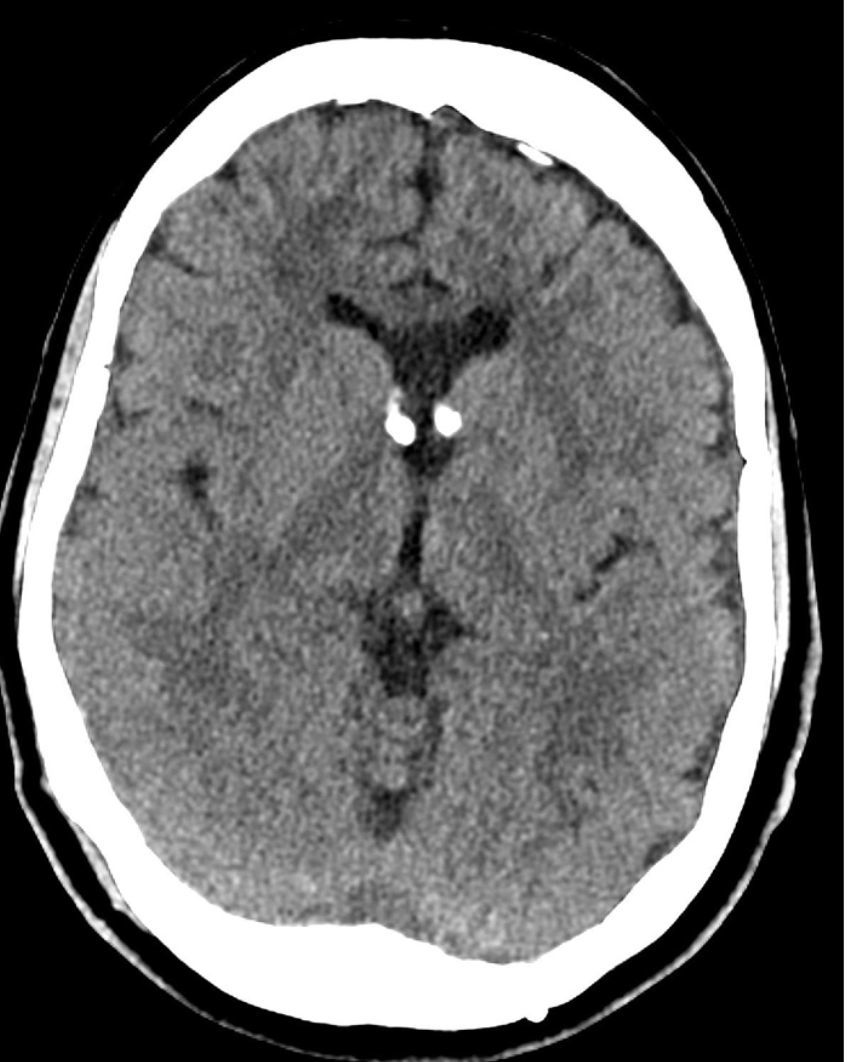

Diagnosis of normal pressure hydrocephalus